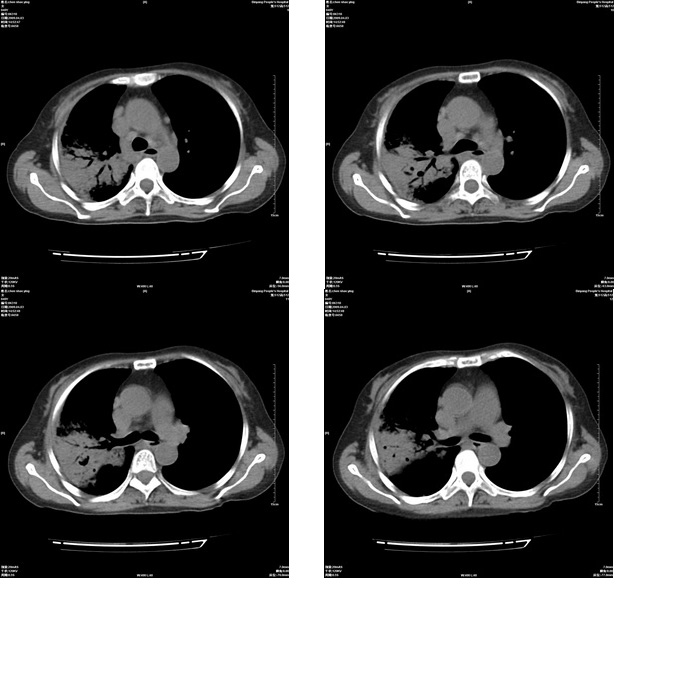

患者,女,48岁,发热伴陈发性咳嗽5天,偶尔痰中带血。体温约38°~40°;白细胞明显减低0.85x10的9次方/升。入院后抗炎、抗痨一周复查病灶明显进展。

右上肺后段实变影,内见支气管气象,肺门未见软组织肿块,气管前方有肿大淋巴结。左下肺见多个类圆形结节影。考虑:1.右上肺后段大叶性肺炎,需进一步检查病原体种类,应多询问病史,条件许可考虑做纤支镜检查2.左下肺结节影性质待定

考虑右上肺后段大叶性肺炎不除外结核,伴双肺结节播散灶,希定期复查。

问题是抗炎治疗一个星期后病灶进展。

右肺于酪性肺炎并左肺播散。

考虑两肺继发性肺结核(右肺上叶干酪性肺炎)。

右肺干酪性肺炎并左肺播散。

右肺片状实变影,左肺结节影,抗炎及抗捞治疗后病灶进展。

我考虑:不能除外肺炎型肺泡癌可能。建议查痰或活检。